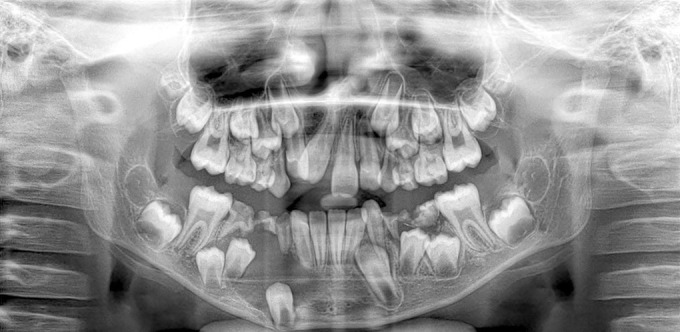

Case description: We present a case of an 8-year-old male who was diagnosed with a mural type of CAF. The patient presented with facial asymmetry and painless swelling of the right mandible. Diagnosis was confirmed through clinical, radiographic, and histopathological examinations, following which a management plan involving the extraction of affected teeth and the surgical excision of the lesion was performed. A 2-year follow-up showed no recurrence.